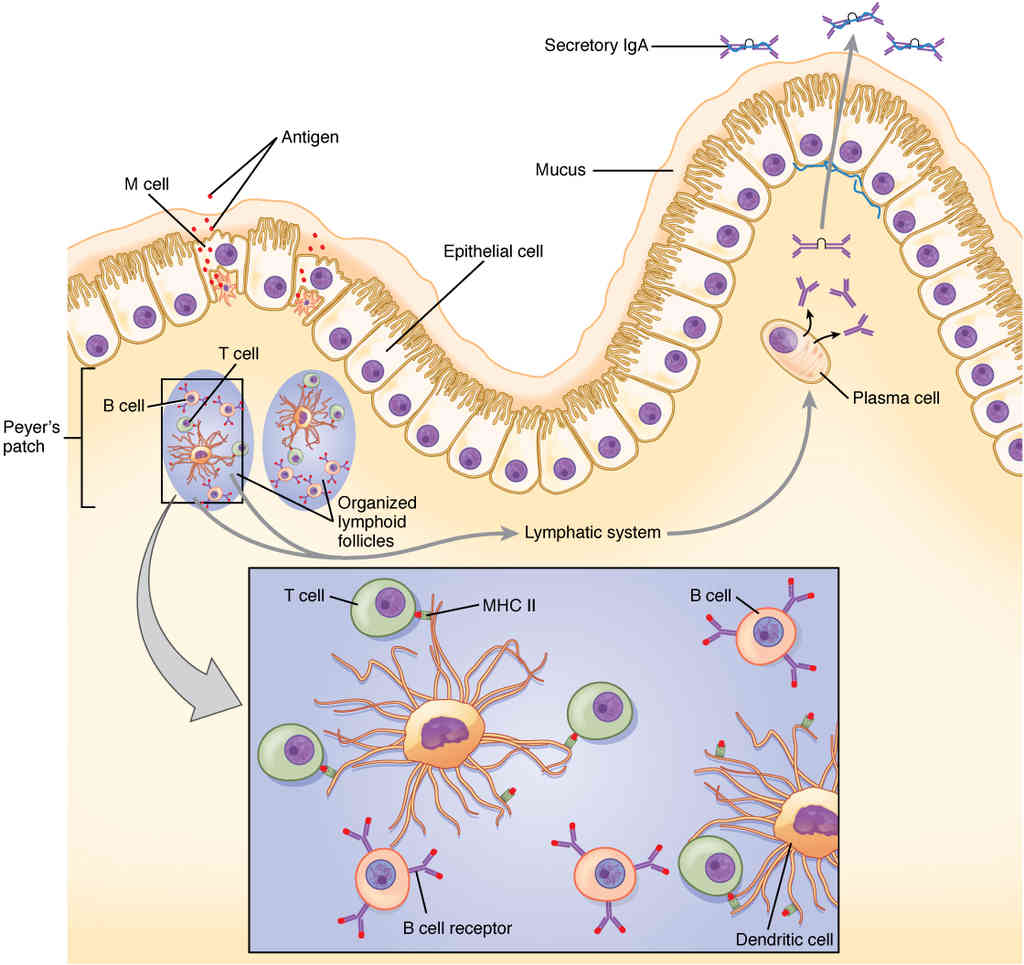

This page is under construction. For now, it is just a resource of the images found in the OpenStax Anatomy and Physiology Handbook. It wil slowly change into a revision tool. Each slide has a number. Use this to refer to the slide. When completed, it will have an unlabelled section, with labelled slides in parallel. On the unlabelled slides, write your answer and use the labelled slide to assess yourself. Keep track by also noting the number on each slide. Improvement at each attempt is important, more so than full marks on a first attempt.